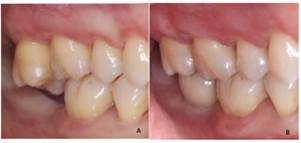

Se presenta a consulta una paciente de género femenino de 56 años, que su motivo de consulta es “necesito un implante”. En el interrogatorio de la historia clínica la paciente no presenta antecedentes patológicos ni no patológicos, por lo que fue clasificada como ASA I11. A la exploración clínica se observó la ausencia del segundo molar inferior derecho (4.7), el cual, refiere la paciente, perdió por caries. A su vez, se encontró la extrusión del molar antagonista (1.7) hacia el área a rehabilitar e inflamación gingival inducida por placa (Fig. 1).

Al finalizar el tratamiento se logró la intrusión de 4mm del segundo molar superior derecho sin complicaciones en el diente adyacente en 4 meses y la sustitución del espacio ausente del segundo molar inferior derecho por un implante dental. La paciente no refirió sintomatología de la ATM. Se le hizo hincapié sobre la importancia de continuar con su fase de mantenimiento cada 3 meses para asegurar salud periimplantaria y periodontal.